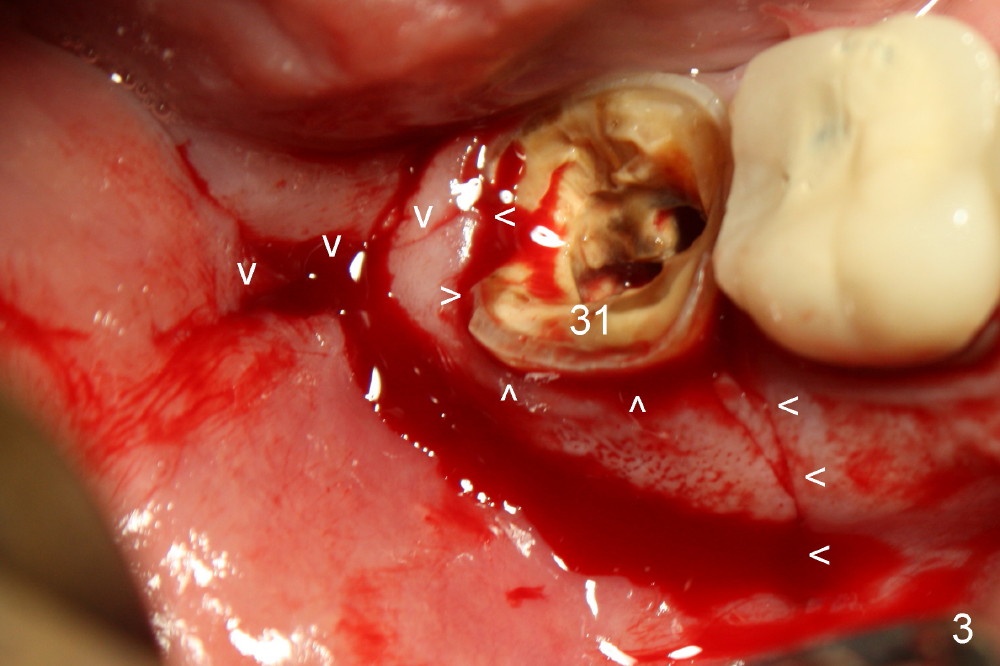

Immediate Implant Next to Dentigerous Cyst

A 47-year-old man requests restoring the tooth #31 (Fig.1). It appears

that the best option is an implant. A close look reveals a possible cyst

(arrowheads) associated with #32. On the day of surgery, a panoramic X-ray

is taken (Fig.2). The cyst is to be enucleated while an immediate implant

is to be placed in the mesial socket of #31. An incision is made as

indicated by Fig.3 arrowheads. The bone is resorbed on the top of the cyst